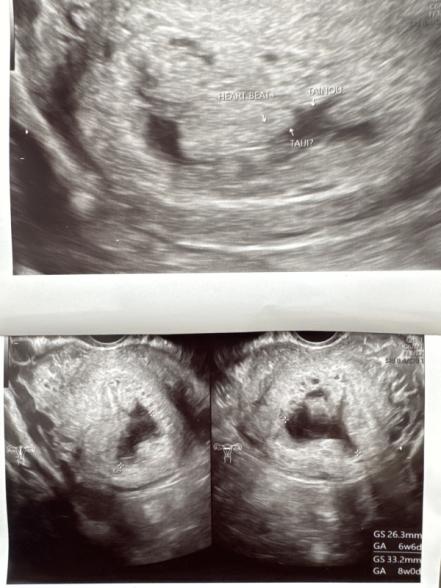

昨日、心拍確認のため再診にいきました。心拍はあるものの胎芽が不明瞭ではっきりとは分からずでした。

心拍は見えるけど胎芽が分かりにくい原因は何なのでしょうか?たしかに、胎芽意外にも白い部分が多く、エコーも見にくかったです。卵黄嚢も分からずだったので、先生からは今回は厳しいかもと話はありました。